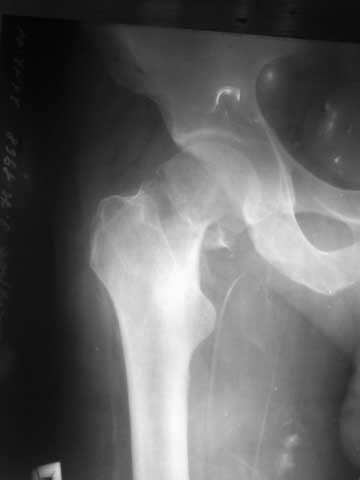

[Ortho] перелом шейки бедра

р-снимок своего брата, 43года, с переломом шейки бедра. Снимок не очень качественный, пока

других нет, кажется, перелом субкапитальный, линия излома косая, похоже В2,2 по АО,или

Паувельс- 2,. Просит, если можно, чтобы наш форум помог советом, каким способом лечить

брата.